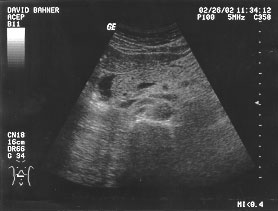

Gallbladder (unlabeled)